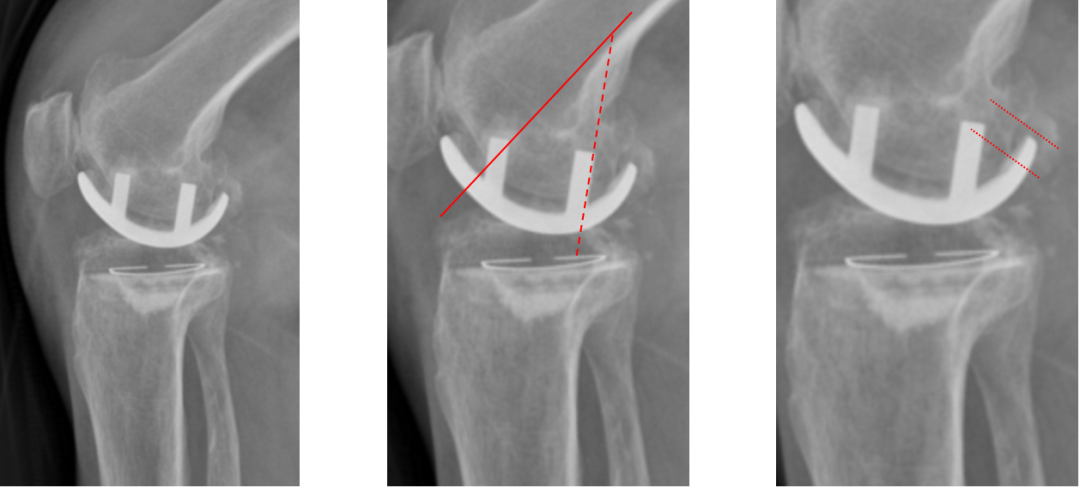

侧位片标准胫骨和股骨假体位置

侧位片假体位置:股骨假体长栓与短栓平行,后倾35°;假体后缘与股骨后髁齐平,胫骨假体后倾7°,与胫骨平台前后缘齐平。

股骨假体偏小

侧位片股骨假体位置:股骨假体偏小,与胫骨假体后缘不齐平;屈曲15°,未包容股骨后髁。

股骨假体偏大

侧位片股骨假体位置:股骨假体与胫骨假体不匹配,股骨假体大一个型号,屈曲45°,后缘空虚。

股骨假体屈曲角度大

侧位片股骨假体位置:股骨假体与胫骨假体匹配,股骨假体屈曲62°,前缘翘起。